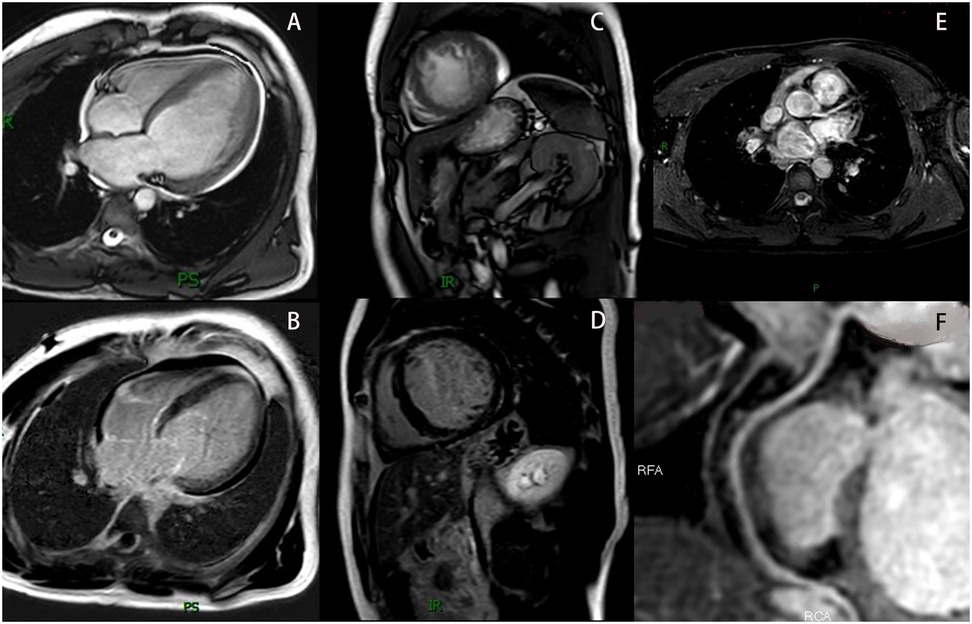

To identify the cause of heart failure, additional examinations were performed. Laboratory tests showed hyperlipidemia (cholesterol 5.30 mmol/L, LDL-C 3.69 mmol/L), elevated B-type natriuretic peptide (BNP 479.91 pg/mL), and positive urine occult blood (+). Other tests including complete blood count, coagulation profile, D-dimer, liver function, kidney function, blood glucose, electrolytes, thyroid function, iron studies, autoimmune markers, and urinary microalbumin-to-creatinine ratio (ACR) were normal. A 24 h Holter EKG showed occasional atrial premature contractions, ventricular premature beats, and short-duration ventricular tachycardia. Coronary magnetic resonance angiography (CMRA) revealed no obstructive coronary artery disease (Figures 2E,F). Cardiac magnetic resonance imaging (MRI) demonstrated: enlarged left ventricular end-diastolic volume (EDV) of 179.9 mL, LVED of 60 mm, depressed LVEF of 21%, reduced cardiac output (CO) of 2.8 L/min, and hypertrabeculation with wall thinning (Figures 2A,C). T1 mapping values and extracellular volume were normal, with no significant perfusion reduction during first-pass myocardial perfusion or abnormal enhancement on delayed imaging (Figures 2B,D).

Figure 2

The patient's MRI results. (A) Show the cardiac MRI four-chamber image. (B) Show the LGE image in the four-chamber view. (C) Show the cardiac MRI short-axis image. (D) Show the LGE image in the short-axis view. (E) Show the LAD in the CMRA (The LCX was not visualized due to its diminutive caliber). (F) Show the RCA in the CMRA. MRI, magnetic resonance imaging; LGE, late gadolinium enhancement; LAD, left anterior descending artery; LCX, left circumflex artery; RCA, right coronary artery coronary; CMRA, coronary magnetic resonance angiography.